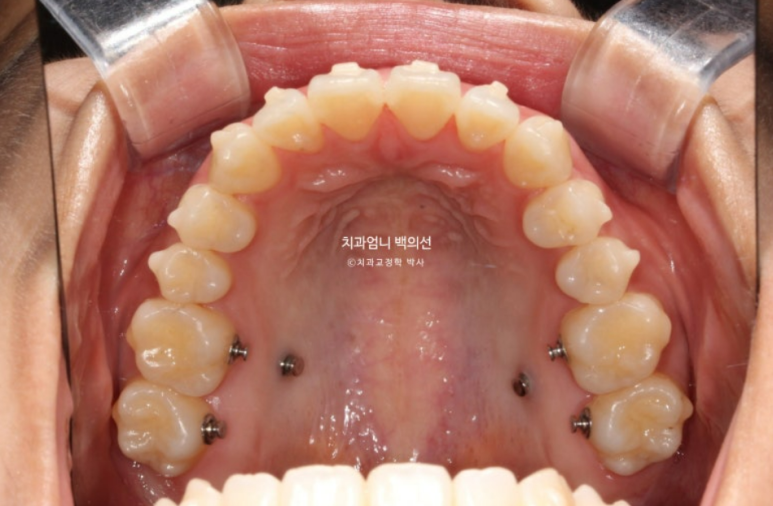

23년 12월 1번장치를 끼기 시작해서 25년 1월까지 총 51개 장치를 다 낀 후 모습입니다.

앞니 개방교합은 해소가 되었지만 앞니 중심선 불일치가 약 1mm 남았습니다.

우측 어금니 교합은 약간 떠있는 상태이고

좌측 어금니 교합은 좋습니다.

배열도 좋습니다.

교정용 나사는 위 2개 아래 2개 총 4개를 식립해서 진행했습니다.

첫번째 세트 51개 장치 안에서 미니스크류를 이용한 상악 어금니 합입과 하악 어금니 후방이동이 잘 일어났습니다.